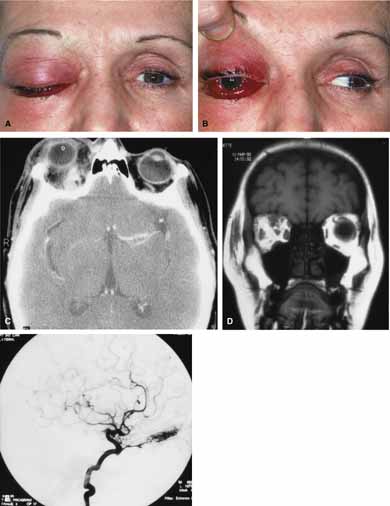

Although there have been a few reports of mucormycosis occurring in healthy individuals, virtually all other patients have had previous severe underlying disease. The patient most vulnerable to this infection is an one with uncontrolled diabetes with ketoacidosis. A host of other conditions also predispose patients to the disease including: multiple myeloma, lymphoma, organ transplantation with immunosuppresion, chemotherapy, corticosteroid treatment, acquired immunodeficiency syndrome, etc.(Fig. 2A).12–14 Mortality is extremely high for patients with phycomycosis infection, and successful treatment is contingent on early recognition and prompt treatment.

Fig. 2 A. A 65-year-old man with a myelodysplastic disorder and pancytopenia developed a pimple on the side of his nose followed by rapidly developing cellulitis and skin necrosis. The patient developed a frozen globe and loss of vision over a matter hours. Despite aggressive surgical debridement of the necrotic areas and intravenous, amphotericin, the patient died. B. Black eschar (necrosis) along right side of nose, ala, upper lip, and hard palate. C. Right orbital infiltration is seen along with opacification of the right ethmoid sinus and nasal passage. D. The optic nerve is on stretch with tethering of the globe, extensive soft tissue swelling anteriorly, ethmoidal opacification, and enlargement of the right medial rectus muscle.

A characteristic pattern of clinical symptoms and signs occurs, the recognition of which should lead to the immediate institution of antifungal treatment and possible surgical intervention to increase the patient's chances of survival. Early diagnosis while the disease is still somewhat anatomically confined is essential for a more favorable outcome.12–14

Characteristic features of orbital mucormycosis include an immunocompromised patient with sinusitis, pharyngitis or nasal discharge who develops cellulitis of the face or lid. Signs and symptoms include orbital/periorbital pain, acute proptosis, abrupt visual loss, orbital apex syndrome with acute motility changes (external ophthalmoplegia), pupillary changes (internal ophthalmoplegia), ptosis, and decreased corneal sensation. Infarction of tissue results in black eschar formation of the skin, nasal mucosa and hard palate (Fig. 2A and 2B).12,13 With intracranial extension, the patient generally become obtunded, develops convulsions, contralateral hemianaesthesia or hemiplegia, and lapses into coma.

CT scanning demonstrates an orbital mass often with bone destruction and sinus involvement (Fig. 2C and 2D). The diagnosis is confirmed by biopsy of involved tissue with demonstration of characteristic nonseptate, large, branching hyphae, which can be seen on routine hematoxylin and eosin stains. Material should be submitted for both frozen and conventional paraffin-embedded sections. Frozen sections are not always definitive and the surgeon must have considerable confidence in the skill of the pathologist. 13 Management includes: (1) early definitive diagnosis; (2) correction of any underlying metabolic disturbance; (3) wide local excision with debridement of all involved and devitalized oral, nasal, sinus and orbital tissue; (4) establishment of adequate sinus and orbital drainage; (5) daily irrigation and packing of the involved orbital and paranasal areas with amphotericin B; and (6) intravenous amphotericin B.12,13,15